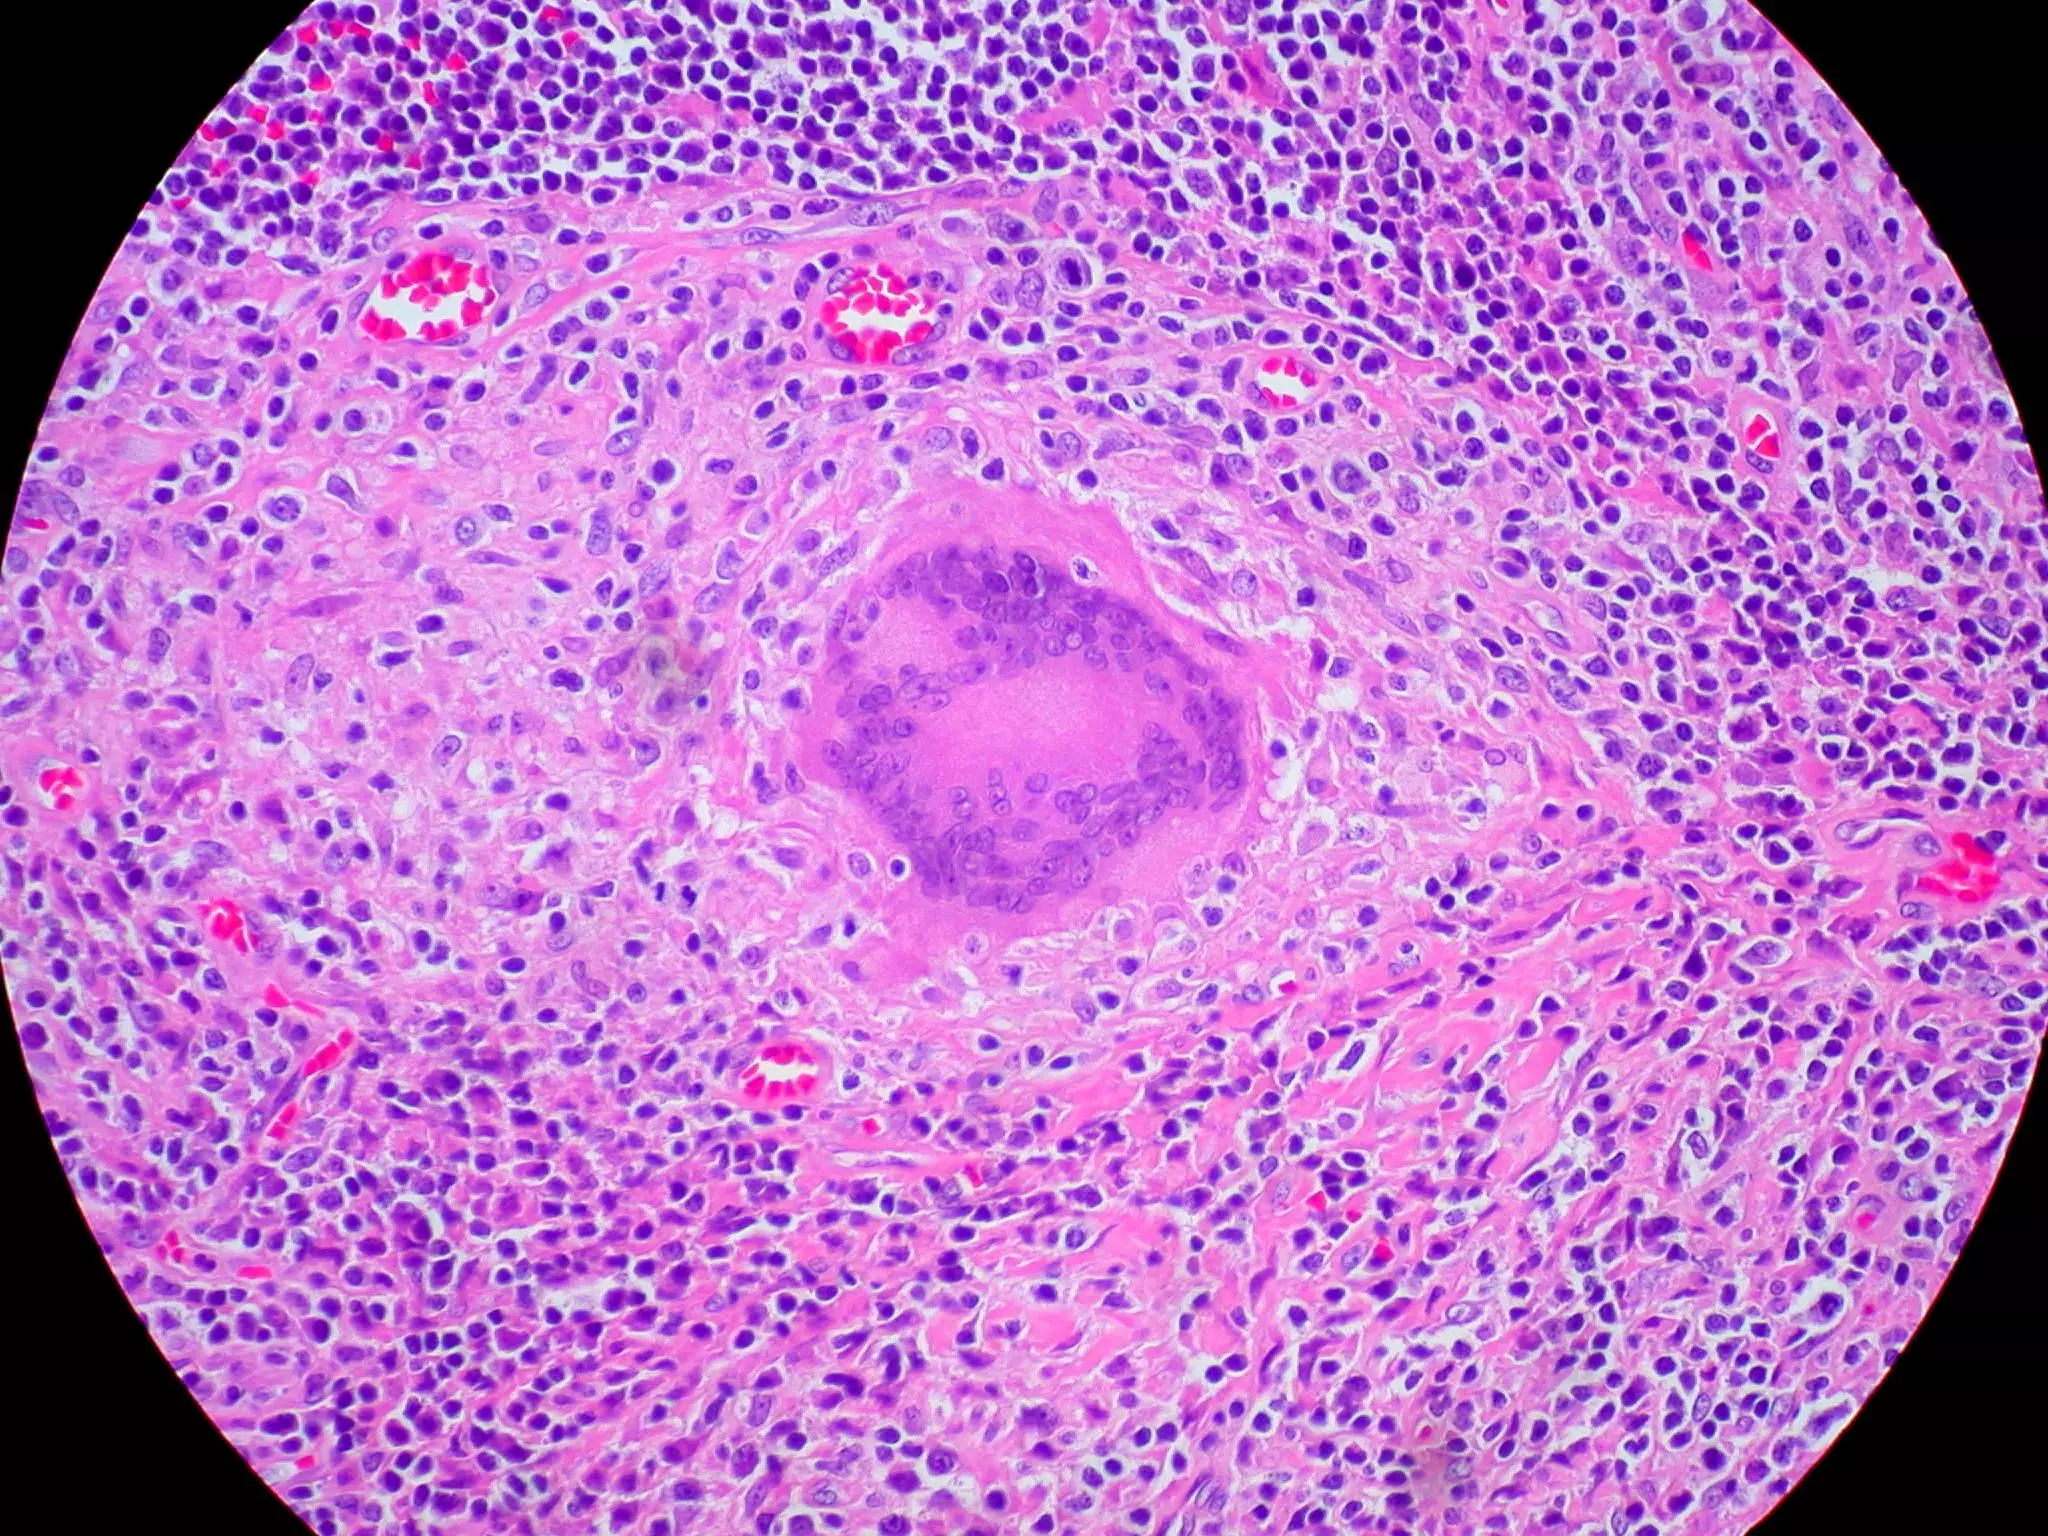

Langhans Giant Cells - nuclei are arranged in the peripheral area of the giant cell. They are typically seen in tuberculosis (TB). The typical bacteria that causes TB, Mycobacterium tuberculosis, has a waxy capsule that resists digestion by macrophages. Macrophages therefore form a giant cell around the mycobacterium to isolate and contain it.

Image - Histological Sample Showing a Langhans Type Giant Cell

Creative commons source by Ed Uthman [CC BY-SA 4.0 (https://creativecommons.org/licenses/by-sa/4.0)]